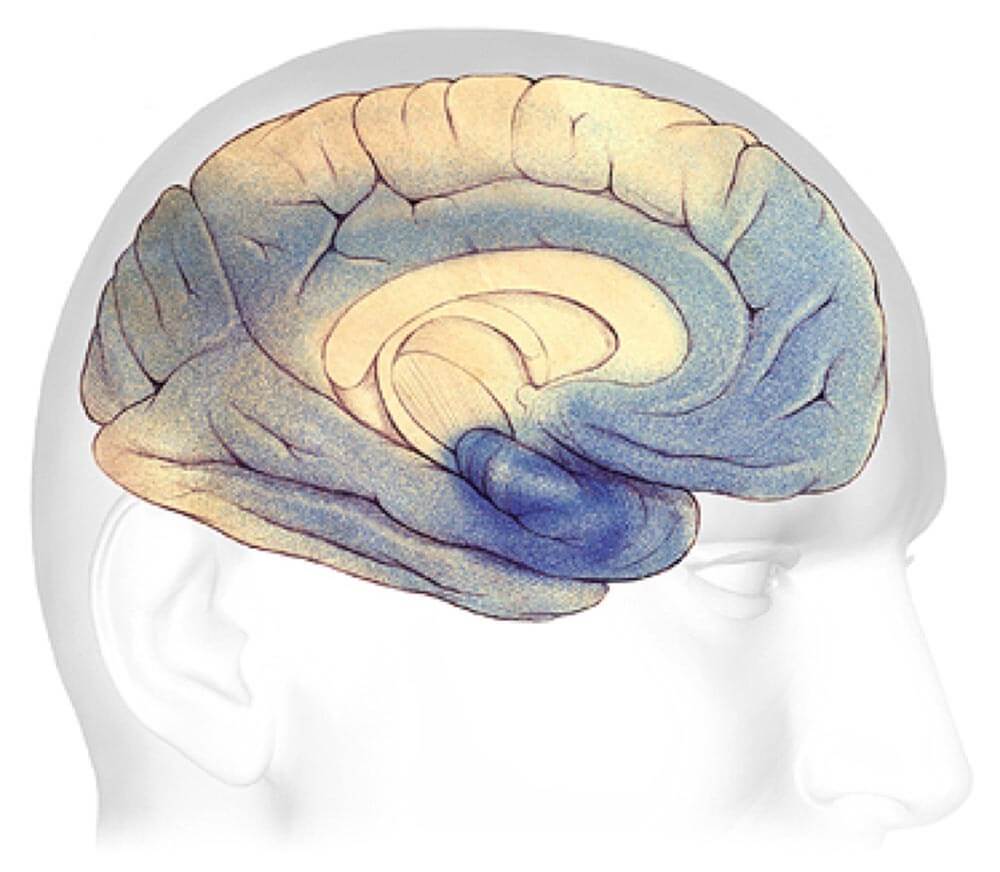

Alzheimer's disease leads to nerve cell death and tissue loss throughout the brain. Over time, the brain shrinks dramatically, affecting nearly all its functions.

These images show:

A brain without the disease.

A brain with advanced Alzheimer's.

How the two brains compare.

Plaques and tangles (shown in the blue-shaded areas) tend to spread through the cortex in a predictable pattern as Alzheimer's disease progresses. The rate of progression varies greatly. On average, a person with Alzheimer's lives four to eight years after diagnosis, but can live as long as 20 years, depending on other factors. The course of the disease depends in part on age at diagnosis and whether a person has other health conditions.

Earliest Alzheimer's - changes may begin 20 years or more before diagnosis.

Mild to moderate Alzheimer's stages - generally last from 2 - 10 years.

Severe Alzheimer's - may last from 1 - 5 years.

Earliest Alzheimer's Stages

In the earliest stages, before symptoms can be detected with current tests, plaques and tangles begin to form in brain areas involved in:

Learning and Memory

Thinking and Planning

Mild to Moderate Alzheimer's

In mild to moderate stages, brain regions important in memory and thinking and planning develop more plaques and tangles than were present in early stages. As a result, individuals develop problems with memory or thinking serious enough to interfere with work or social life. They may also get confused and have trouble handling money, expressing themselves and organizing their thoughts. Many people with Alzheimer's are first diagnosed in these stages.

As Alzheimer's progresses, individuals may experience changes in personality and behavior and have trouble recognizing friends and family members.

Plaques and tangles also spread to areas involved in:

Speaking and Understanding Speech

Your sense of where your body is in relation to objects around you

Severe Alzheimer's Disease

In advanced Alzheimer's disease, most of the cortex is seriously damaged. The brain shrinks dramatically due to widespread cell death. Individuals lose their ability to communicate, to recognize family and loved ones and to care for themselves.